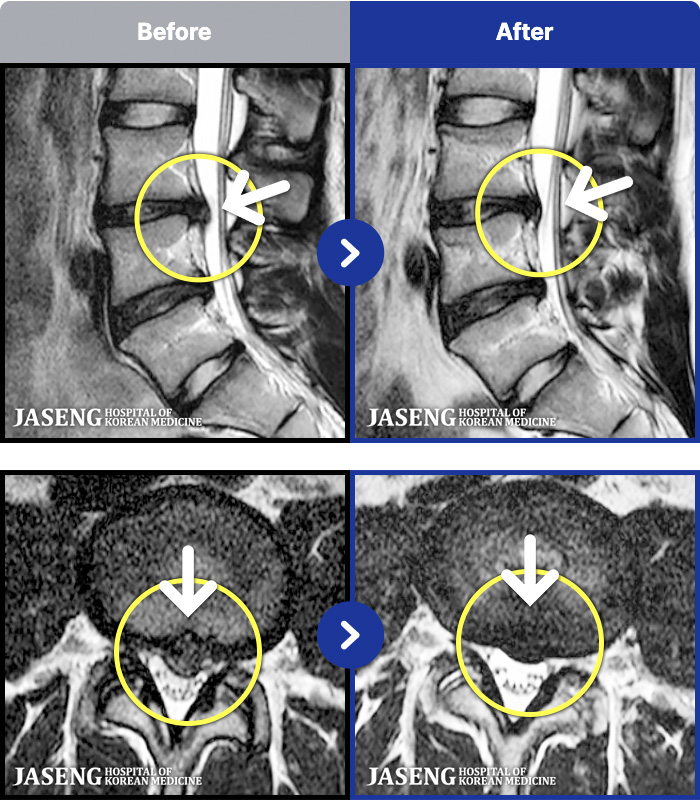

MRI ġ

1,299 MRI ũ ʸ Ȯϼ.